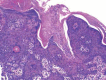

Porokeratosis is a skin disorder clinically characterized by annular plaques with keratotic borders resembling the Great Wall of China and histopathologically by cornoid lamellae. The disease has several clinical variants. Porokeratosis ptychotropica, which has recently become part of these variants, is quite rare and little known. The entity is characterized by verrucous plaques - which may resemble a psoriasis plaque - that affect the regions of the buttocks, most commonly the gluteal cleft, with or without extremity involvement. Itching is often present. We report a rare case of porokeratosis ptychotropica and highlight its unusual manifestation (single plaque), the first case reported in the Brazilian literature.